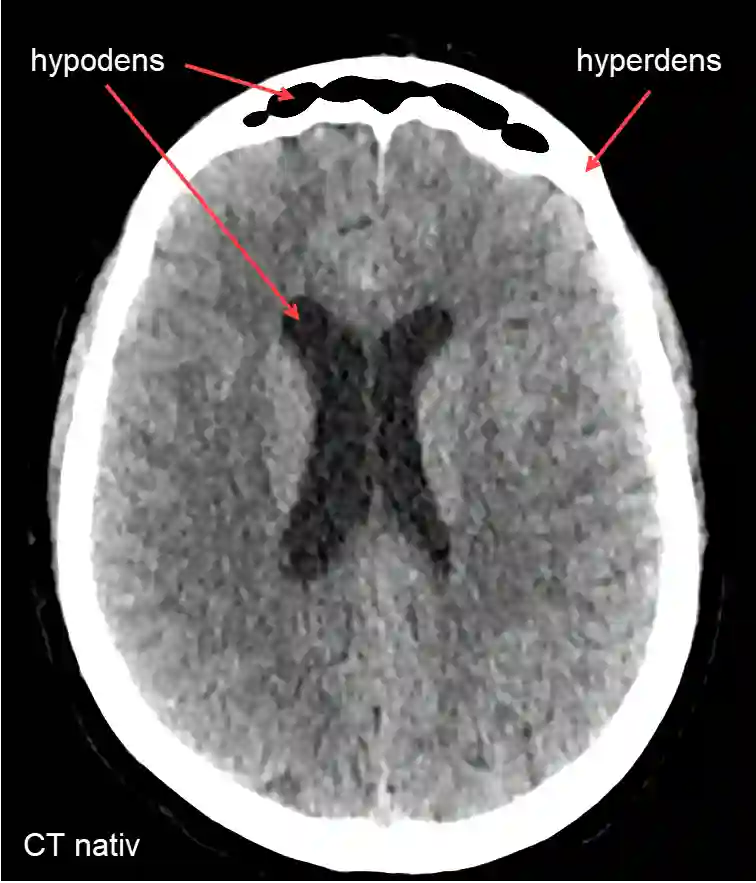

In CT imaging, a hyperdense area is defined as a region that possesses increased optical density and therefore appears brighter in the image.

Figure

Hypodensity and hyperdensity on CT